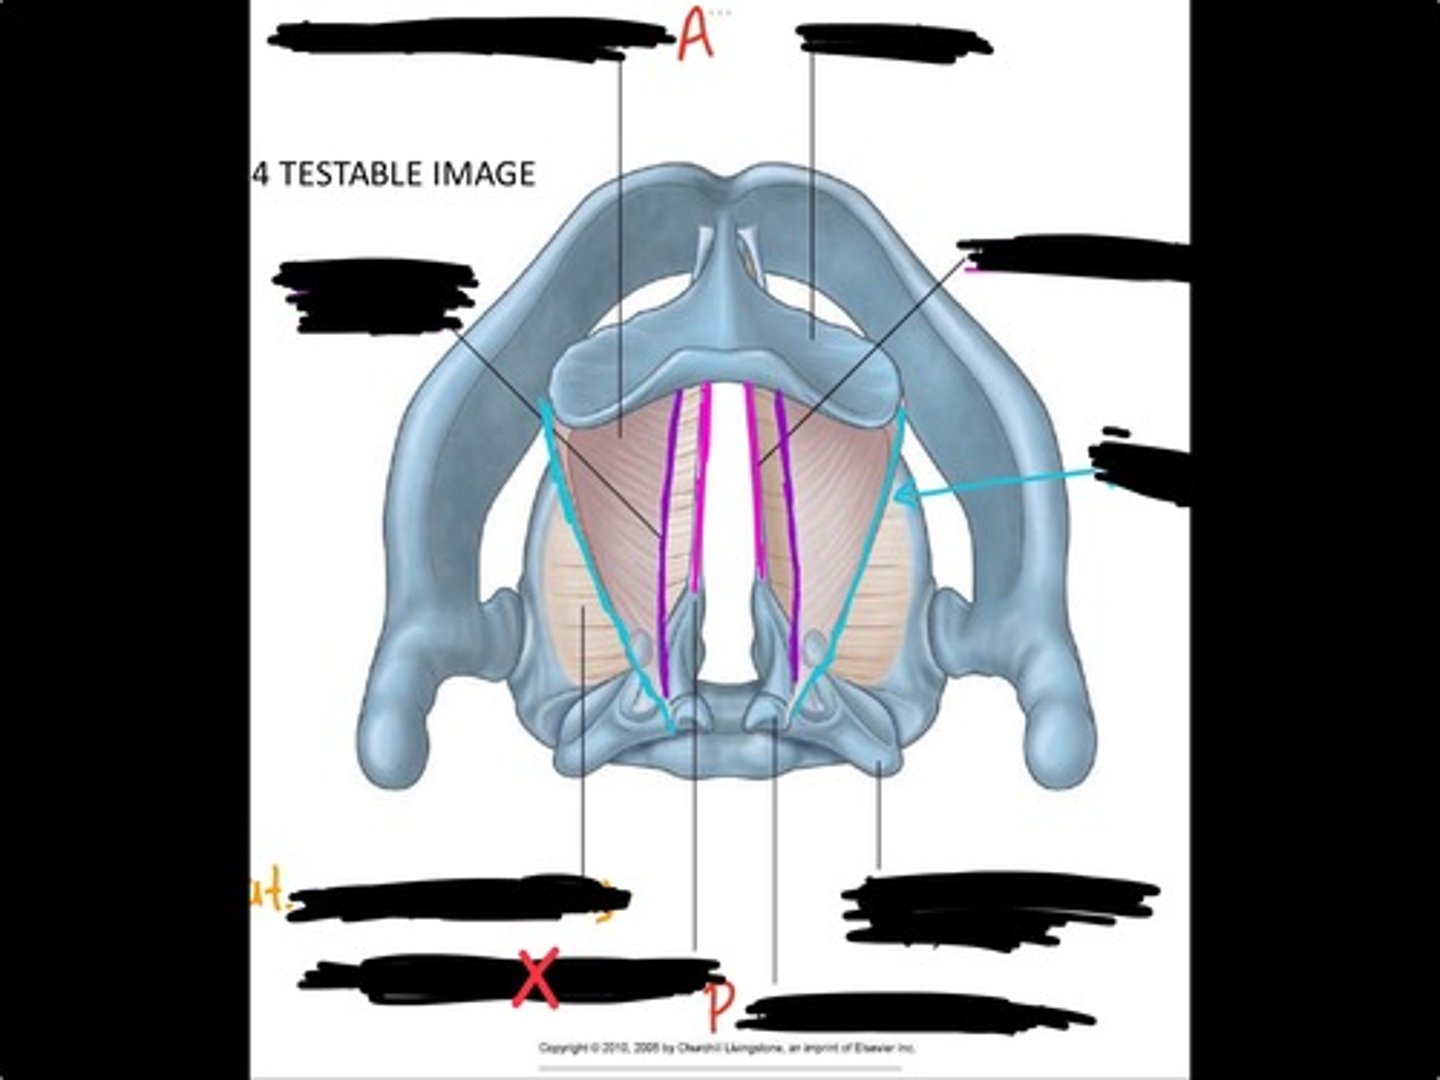

Vocal process of arytenoid

Conus elasticus

Vestibular ligament

Quadrangular membrane

Epiglottis

vocal ligament

Aryepiglottic ligament

Muscular process of arytenoid

Corniculate cartilage

Posterior crico arytenoid

oblique arytenoid

transverse artyenoid

Rima glottidis

Vocal ligament

Vocalis muscle

Lateral cricothyroid ligament

Lateral cricoartenoid